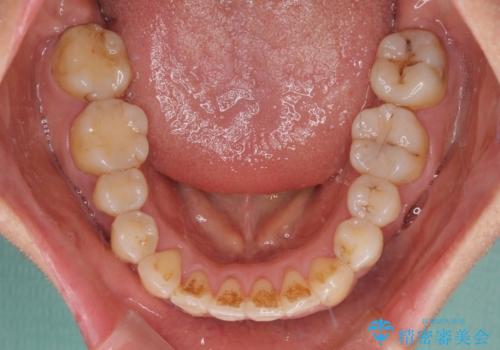

- 上顎の著しい叢生と奥歯の咬みにくさを気にして来院された患者様です。

骨格的に上顎は狭く、下顎は右側にシフトしていたため、右側臼歯はクロスバイトとなっていました。